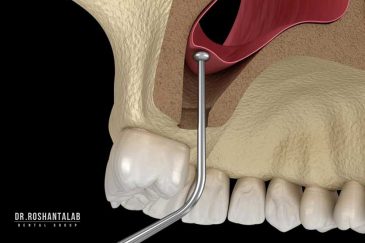

🔸جراحی پیشرفته نظیر سینوس لیفت

تجربه کاشت دندان دیجیتال و بدون درد در ۳ دقیقه! استفاده از برترین برندها زیر نظر جراح، با هزینه مناسب و خدمات کامل از کاشت دندان تا روکشارتودنسی دندان